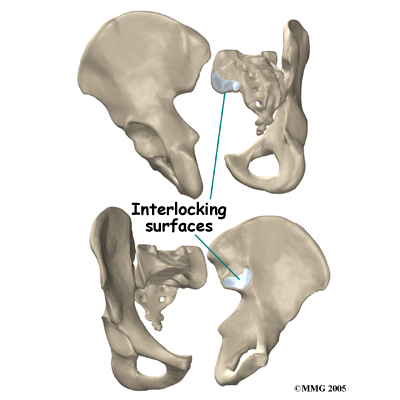

The SI joint is one of the larger joints in the body. The surface of the joint is wavy and fits together similar to the way Lego® pieces fit together. Very little motion occurs in the SI joint compared to most other joints. The motion that does occur is a combination of sliding, tilting and rotation. The most that the joint moves in sliding is probably only a couple of millimeters, and may tilt and rotate two or three degrees.

The SI joint is one of the larger joints in the body. The surface of the joint is wavy and fits together similar to the way Lego® pieces fit together. Very little motion occurs in the SI joint compared to most other joints. The motion that does occur is a combination of sliding, tilting and rotation. The most that the joint moves in sliding is probably only a couple of millimeters, and may tilt and rotate two or three degrees.

The SI joint is one of the larger joints in the body. The surface of the joint is wavy and fits together similar to the way Lego® pieces fit together. Very little motion occurs in the SI joint compared to most other joints. The motion that does occur is a combination of sliding, tilting and rotation. The most that the joint moves in sliding is probably only a couple of millimeters, and may tilt and rotate two or three degrees.

The SI joint is one of the larger joints in the body. The surface of the joint is wavy and fits together similar to the way Lego® pieces fit together. Very little motion occurs in the SI joint compared to most other joints. The motion that does occur is a combination of sliding, tilting and rotation. The most that the joint moves in sliding is probably only a couple of millimeters, and may tilt and rotate two or three degrees.